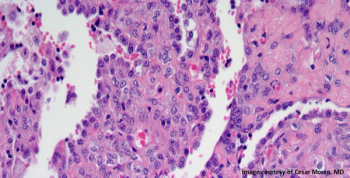

A 36-year-old patient presents with a liver mass, and a biopsy is performed. What is your diagnosis?